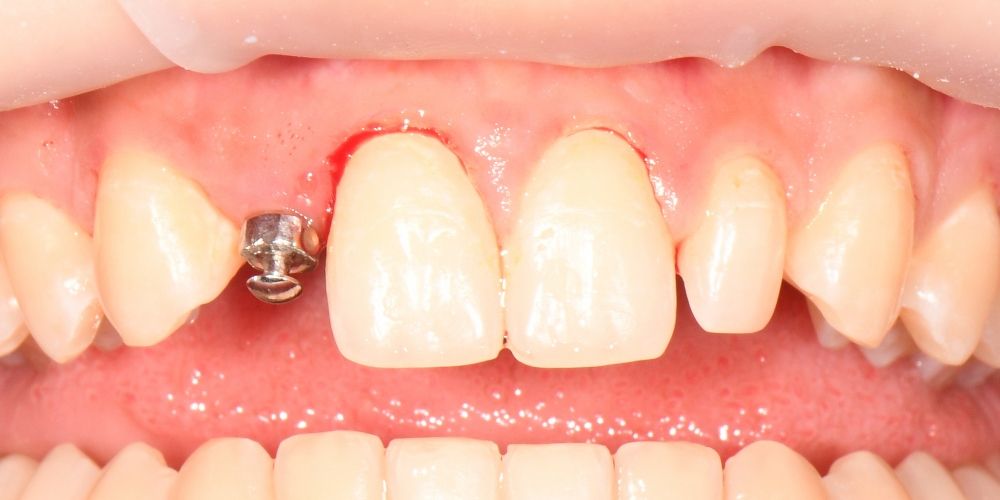

фото коронок

после

до